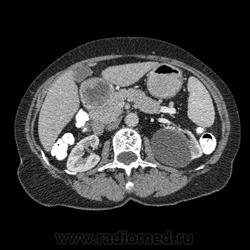

Впечатление, что дуля эта вне головки п.ж., интрамурально в луковице, что ли... тогда возможно GIST, но надо дайком. Утолщение подслизистой в антральном отделе желудка, не удается проследить переход от желудка к 12-перстной((. Внутрипросветно/внутристеночно - не разобрать. 1 фаза?

Клинику! Есть ли признаки высокой тонкокишечной непроходимости, что при ФЭГДС в 12-перстной - туда удалось пройти или нет? ААА! Одни вопросы))))

В-общем, варианты такие без дайкомов: пролапс слизистой в 12перстную, безоар, внутрипросветный дивертикул, гастроинтерстинальная опухоль. И большие сомнения, что это в головке п.ж. - оно отделено от неё тонким слоем жировой клетчатки

Фаз было 3. Видео не выставлял прошлый раз пришел ответ из сайта что видео не работает на сайте Идет накопление контраста в нативе в центре +2+4 по периферии +32+34 .в артериальную +20 и +65 +70 соответственно.

Что оно копит - бог с ним... если это пролапс слизистой, то суммация стенок. Безоар бы не копил. Напрягает отек слизистой в антрале... Это должно быть скорее внутри просвета кишки, т.к. оттесняет газ в 12-перстной на периферию. Без дайкомов больше ничем не могу, извините. Подождём мнения коллег.

Как мне видится - пролапс слизистой желудка в 12-перстную. А мнения коллег что-то нетути...

А что растет из левой почки? Может оно же и желудок сдавливает?

Это расширение всей 12- перстной кишки (стаз).